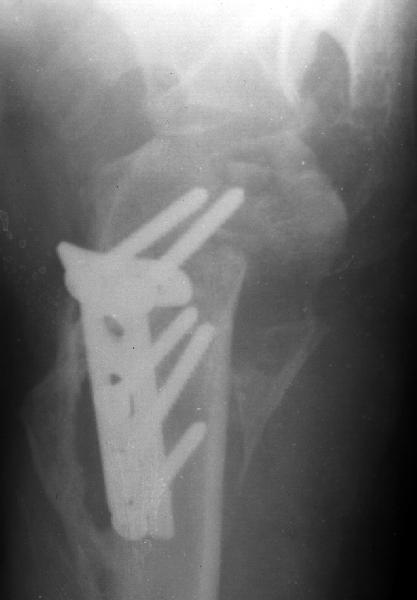

A male 25 y.o. after a car accident Aug 16, 2002 sustained a fracture of the proximal humerus (image 1), Sep 5 ORIF performed elsewhere.

Image 1